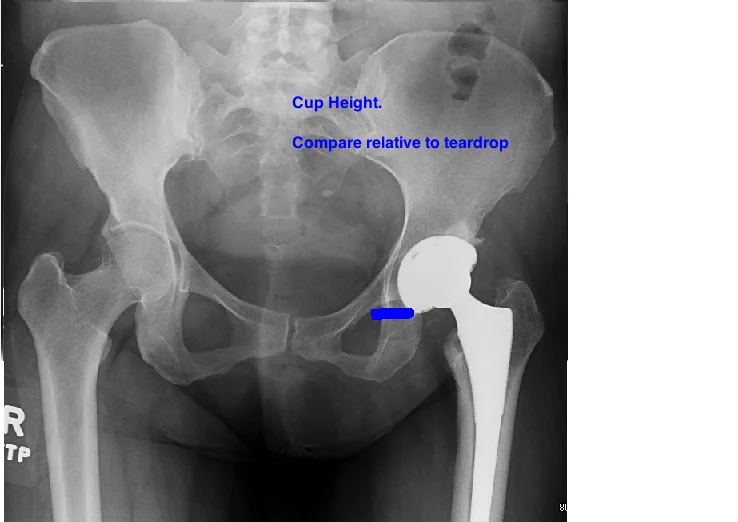

POST-OP EVALUATION

START BY EVALUATING CUP PLACEMENT